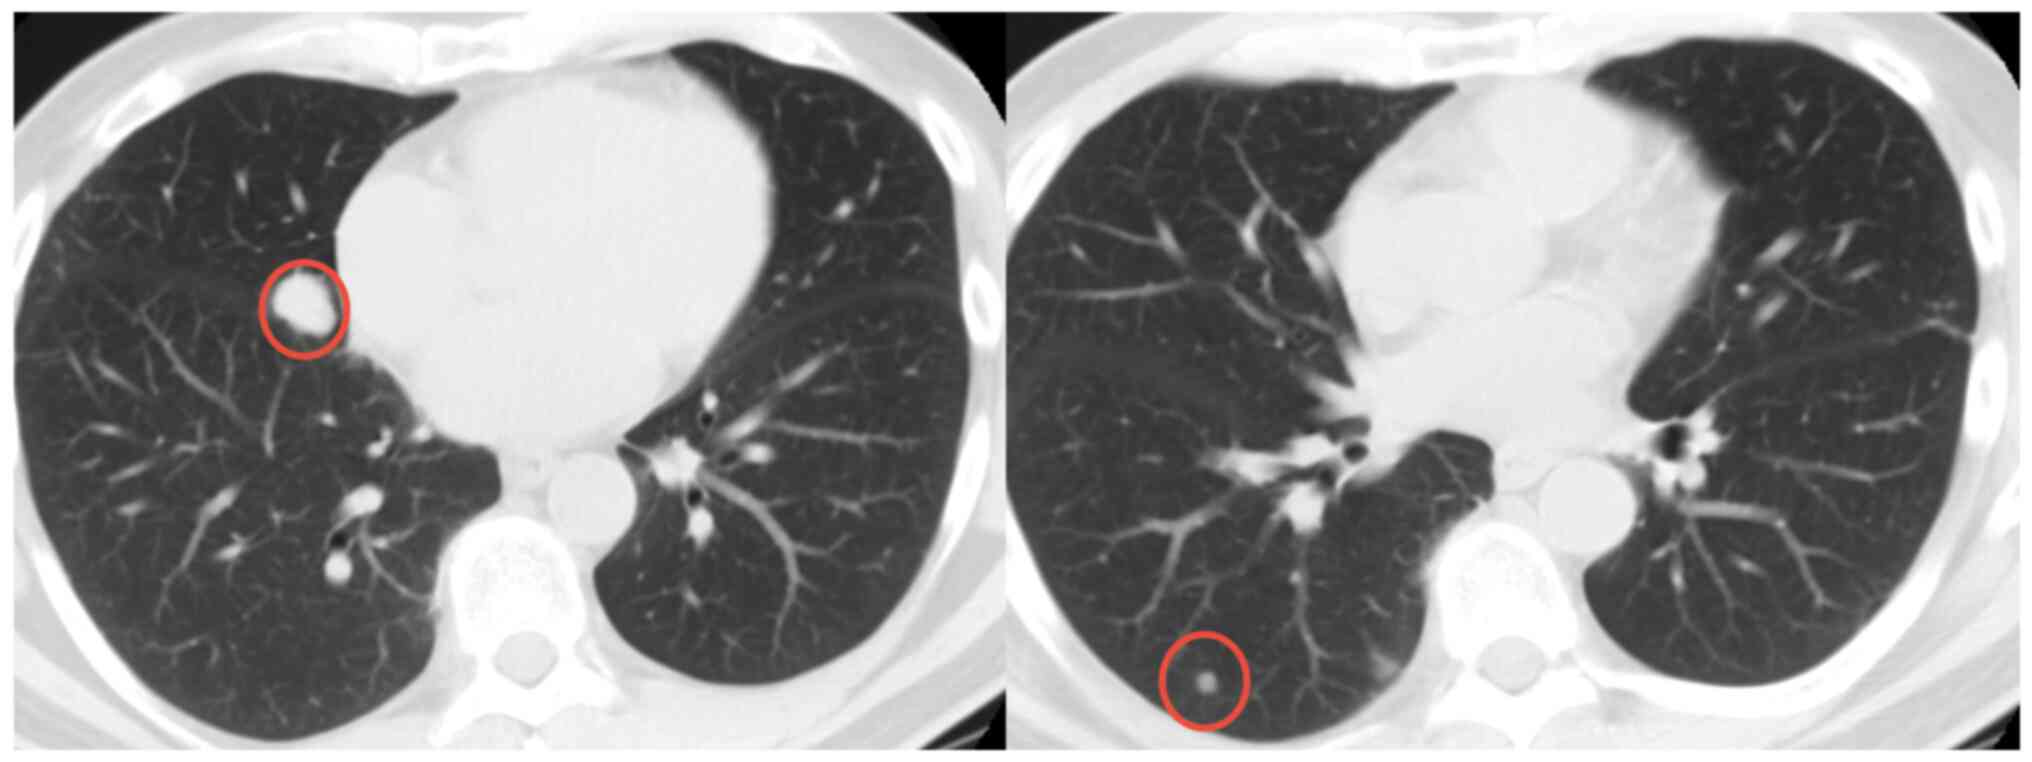

In September 2019, a 46-year-old male patient presented to the Masaryk Memorial Cancer Institute Sarcoma Center (Brno, Czechia) with a 3-month history of pain and swelling in the left hand and wrist. Computed radiography (CR) and MRI scans showed an osteolytic lesion on the base of the fourth metacarpal bone and carpal bones (Fig. 6). The histopathology report indicated a primary malignant GCTB (Fig. 7). CT scans and radiographic imaging showed infiltration of lymph nodes, as well as metastases to the lungs (Fig. 8) and skeleton (Fig. 9). The Musculoskeletal Tumor Committee recommended a radical approach, suggesting amputation of the affected area followed by palliative CHT. The final histopathology report confirmed the presence of a 55-mm high-grade giant cell-rich osteosarcoma (Fig. 10), which was successfully removed through complete resection. The patient passed away 1-year after the surgery.

Figure 8.

Case 2. CT scan showing lung metastases in the patient diagnosed with giant cell-rich osteosarcoma. Red circles indicate the metastases.

In June 2007, a 50-year-old male presented to the Masaryk Memorial Cancer Institute Sarcoma Center, with a 1-month history of persistent pain in the right ankle. Further investigations showed a cystic lesion of the talus on a CR scan, which was later confirmed by a supplementary CT scan (Fig. 16). The histopathology report diagnosed GCTB with a secondary aneurysmal cyst of the talus (Fig. 17), leading to a recommendation for intralesional resection with bone cement augmentation. After receiving the recommended treatment, the patient returned 5 months later with swelling and increased pain in the ankle. A follow-up CT scan showed destruction of the bone surrounding the bone cement, as well as osteolysis of the calcaneus and the presence of an extraosseous mass proximally (Figs. 16 and 18). Due to the extent of osteolysis, the patient required an astragalectomy. Subsequent histopathology reports showed a diagnosis of giant-cell rich osteosarcoma, contradicting the initial findings (Fig. 19). Further staging scans indicated the presence of lung metastases (Fig. 20). The Musculoskeletal Tumor Committee recommended metastasectomy followed by adjuvant CHT. Despite the successful removal of 12 lung metastases, the patient developed additional lung metastases within two months. Despite palliative care efforts, the patient died 6 months later.

Figure 20.

Case 4. CT scan showing multiple lung metastases in the patient diagnosed with giant cell-rich osteosarcoma. Red circles indicate metastases.